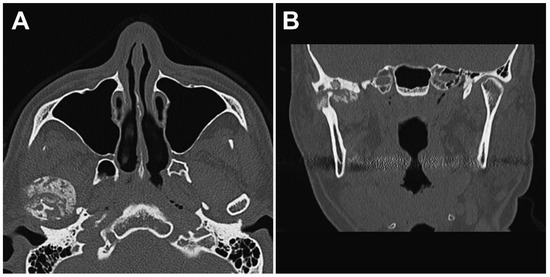

2. Case Presentation

2.1. Clinical Summary

2.2. Pathological Findings